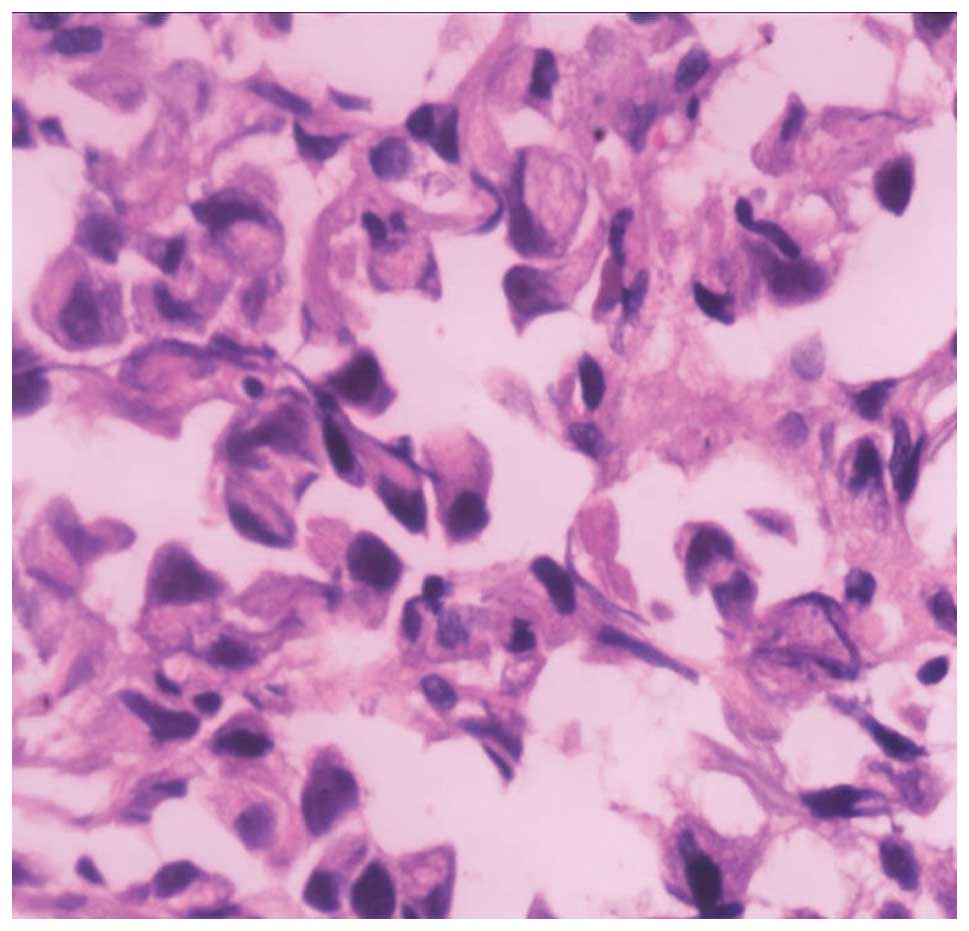

Signet ring cell carcinoma treatment chemotherapy is usually considered the first option for this disease but it has proven to be the least effective for the srcc resulting in lower survival rates. Signet ring cell adenocarcinoma of the colon and rectum is a common colorectal cancer. The treatment you have for signet cell cancer depends on where in the body the cancer starts. Signet ring cell carcinoma srcc is a rare form of highly malignant adenocarcinoma that produces mucin it is an epithelial malignancy characterized by the histologic appearance of signet ring cells.

Signet ring cell adenocarcinoma this may be considered a subtype of colonic type adenocarcinoma or mucinous adenocarcinoma. While it s the most aggressive type and most likely to spread to other. Colorectal cancer is the third most common type of cancer in men and women in the united states. This is because under a microscope the cells look like signet rings.

Histopathological Findings Of The Carcinoma A Signet Ring Cell Download Scientific Diagram